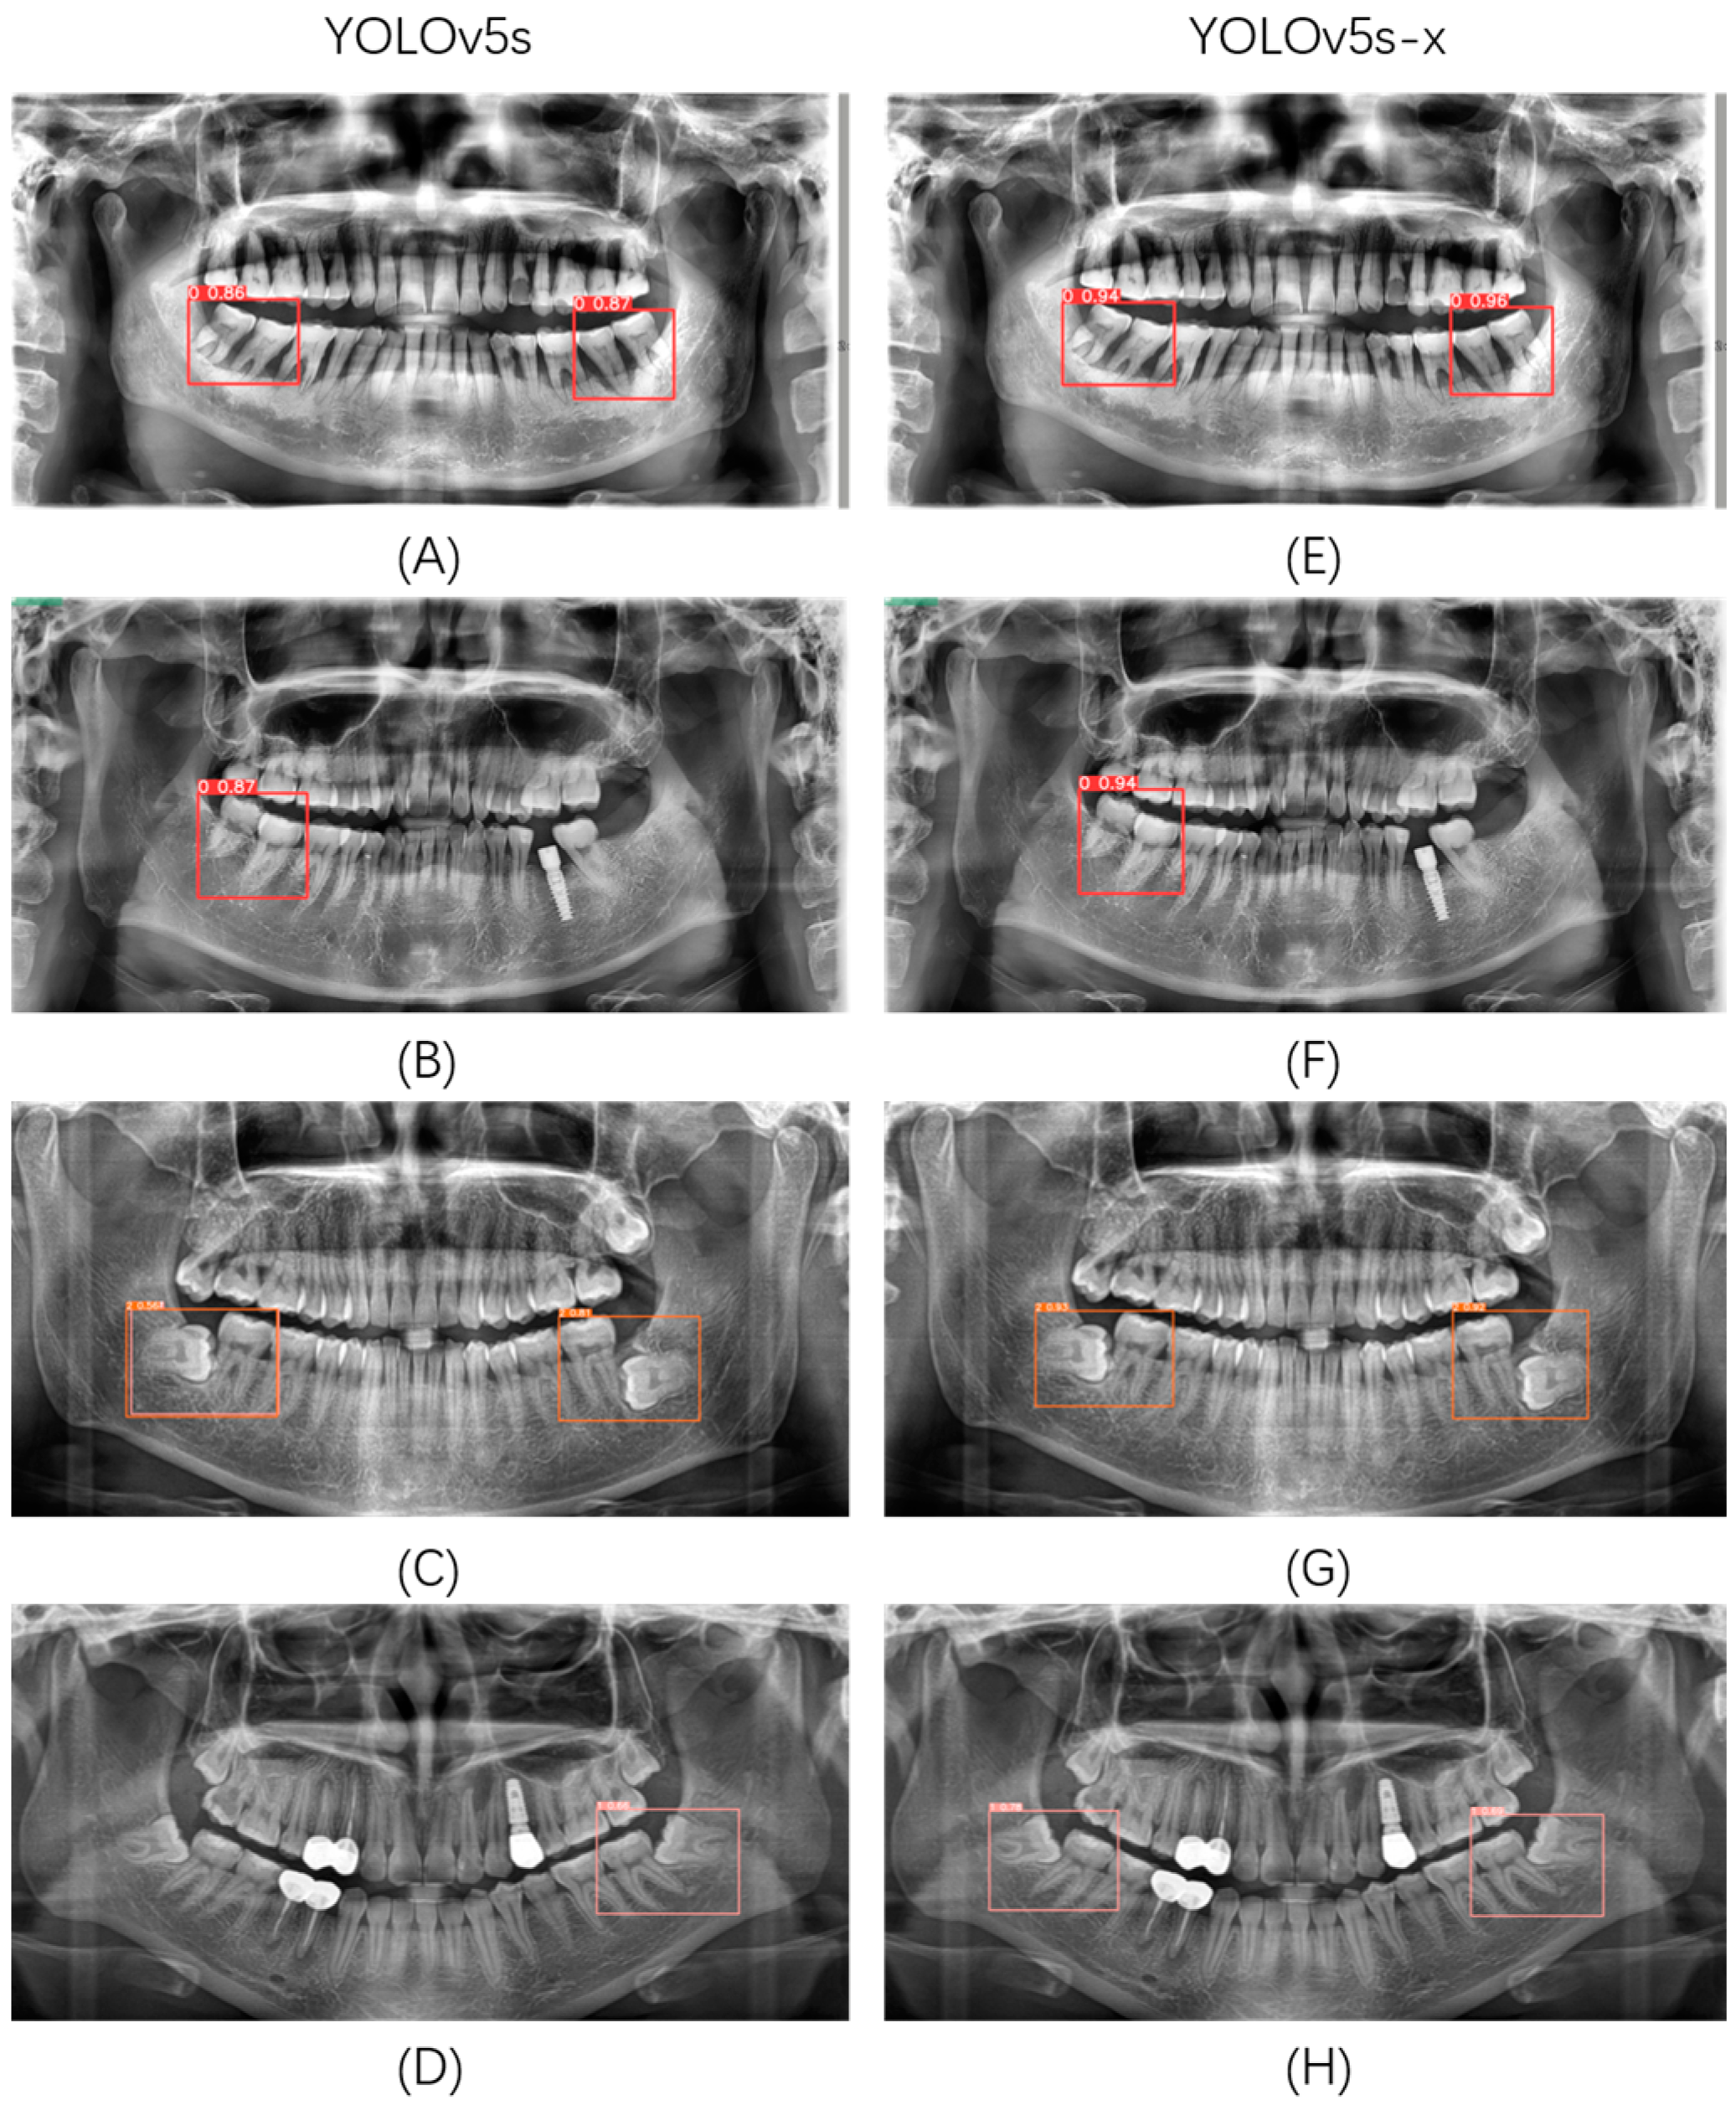

Compared with the original YOLOv5s, YOLOv5s with YOLOv5x as the teacher model (YOLOv5s-x) has a significant advantage in the impacted mandibular third molar detection and classification task. YOLOv5s-x has a 2.9% improvement in mAP, while the number of model parameters and GFLOPs is somewhat reduced. This paper randomly selected several images in the validation set for detection and classification in YOLOv5s and YOLOv5s-x, and the results are shown in Figure 7. It can be seen that YOLOv5s-x alleviates, to a certain extent, the problems of missed, multiple, and wrong detections that exist in YOLOv5s and has a higher detection classification accuracy.

Figure 7. Comparison chart of detection effect. (AD): prediction results of YOLOv5s; (EH): Prediction results of YOLOv5s-x.